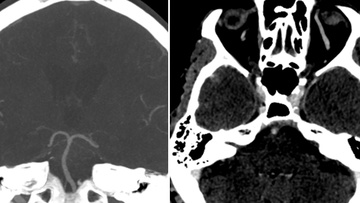

One&Done technique with optiMAX large volume coil

Stent assisted coilingAneurysms